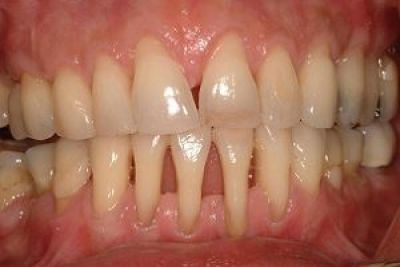

Язвенный гингивит

Воспаление тканей десны, вместе с которым происходит эрозия, изъязвление и некроз десневого края.

Фото 1. Язвенный гингивит обычно причиняет пациентам резкую болезненность десны на фоне имеющегося воспаления.

Симптомы воспаления:

- резкая боль, затрудняющая приём еды;

- наличие неприятного запаха изо рта;

- отёк, кровоточивость дёсен;

- образование на дёснах язв;

- повышенная температура тела;

- общее недомогание.

Важно! Чаще всего язвенный гингивит образуется у людей 18 – 30 лет. Как правило, протекает остро, но при определённых условиях может перейти в подострую или хроническую форму, в язвенный стоматит и пародонтит.